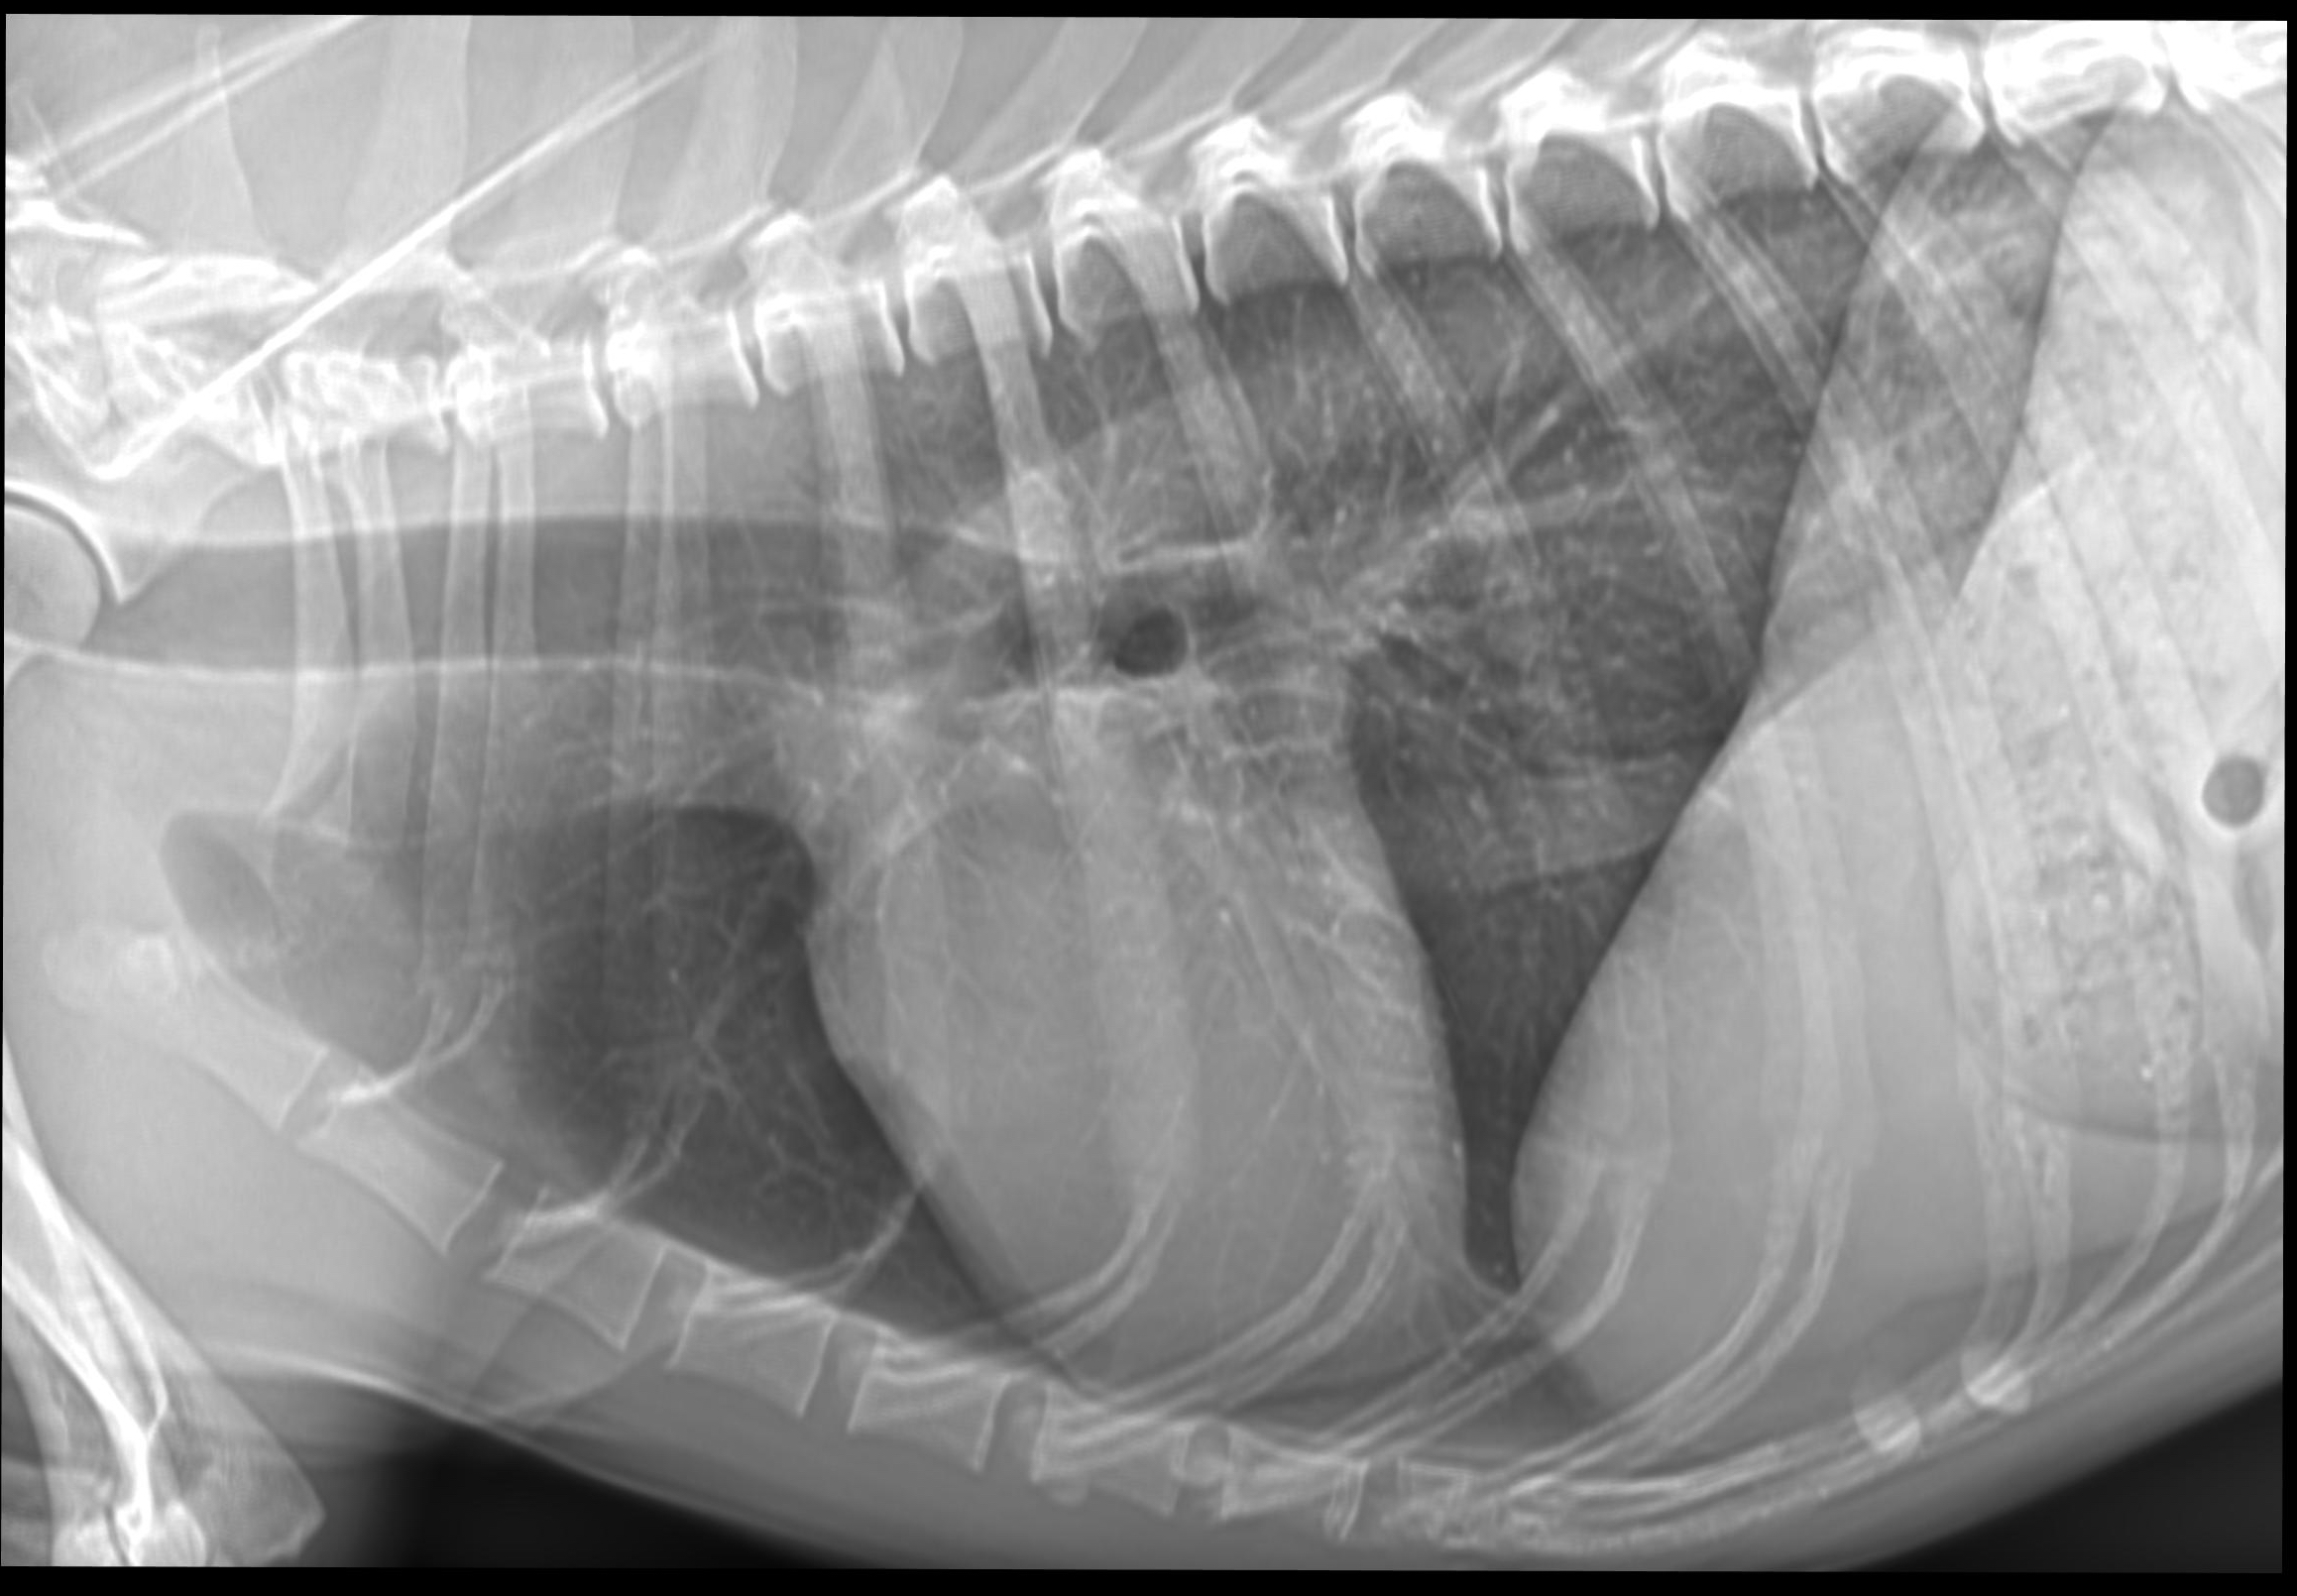

Systemet är en Medivet-byggd lösning där vi själva har valt komponenter och optimerat både applikation, funktion samt bildresultat.

- Leverera en hög och stabil bildkvalitet